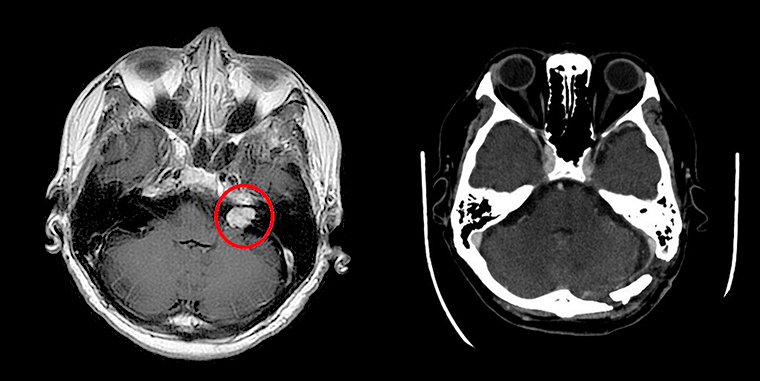

▲術前核磁共振顯示紅圈處有一小於2公分大的腫瘤(左);術後電腦斷層可以確認腫瘤已完整取出(右)。(圖/台北慈濟醫院提供)

徐賢達主任說明,聽神經瘤屬於常見良性腦瘤,根據不同地區和研究,聽神經瘤的盛行率大約在10萬分之1到2左右,多數發生在單側,且生長速度很慢,容易被誤以為是聽力退化,但當腫瘤生長大於2公分且壓迫到聽神經或顏面神經時,就可能會有聽力損失、耳鳴、耳朵有壓力感等症狀,嚴重可能導致平衡異常、面部麻木。若是沒有及時處置,使腫瘤進一步成長壓迫至腦幹,就會有危及生命的風險。